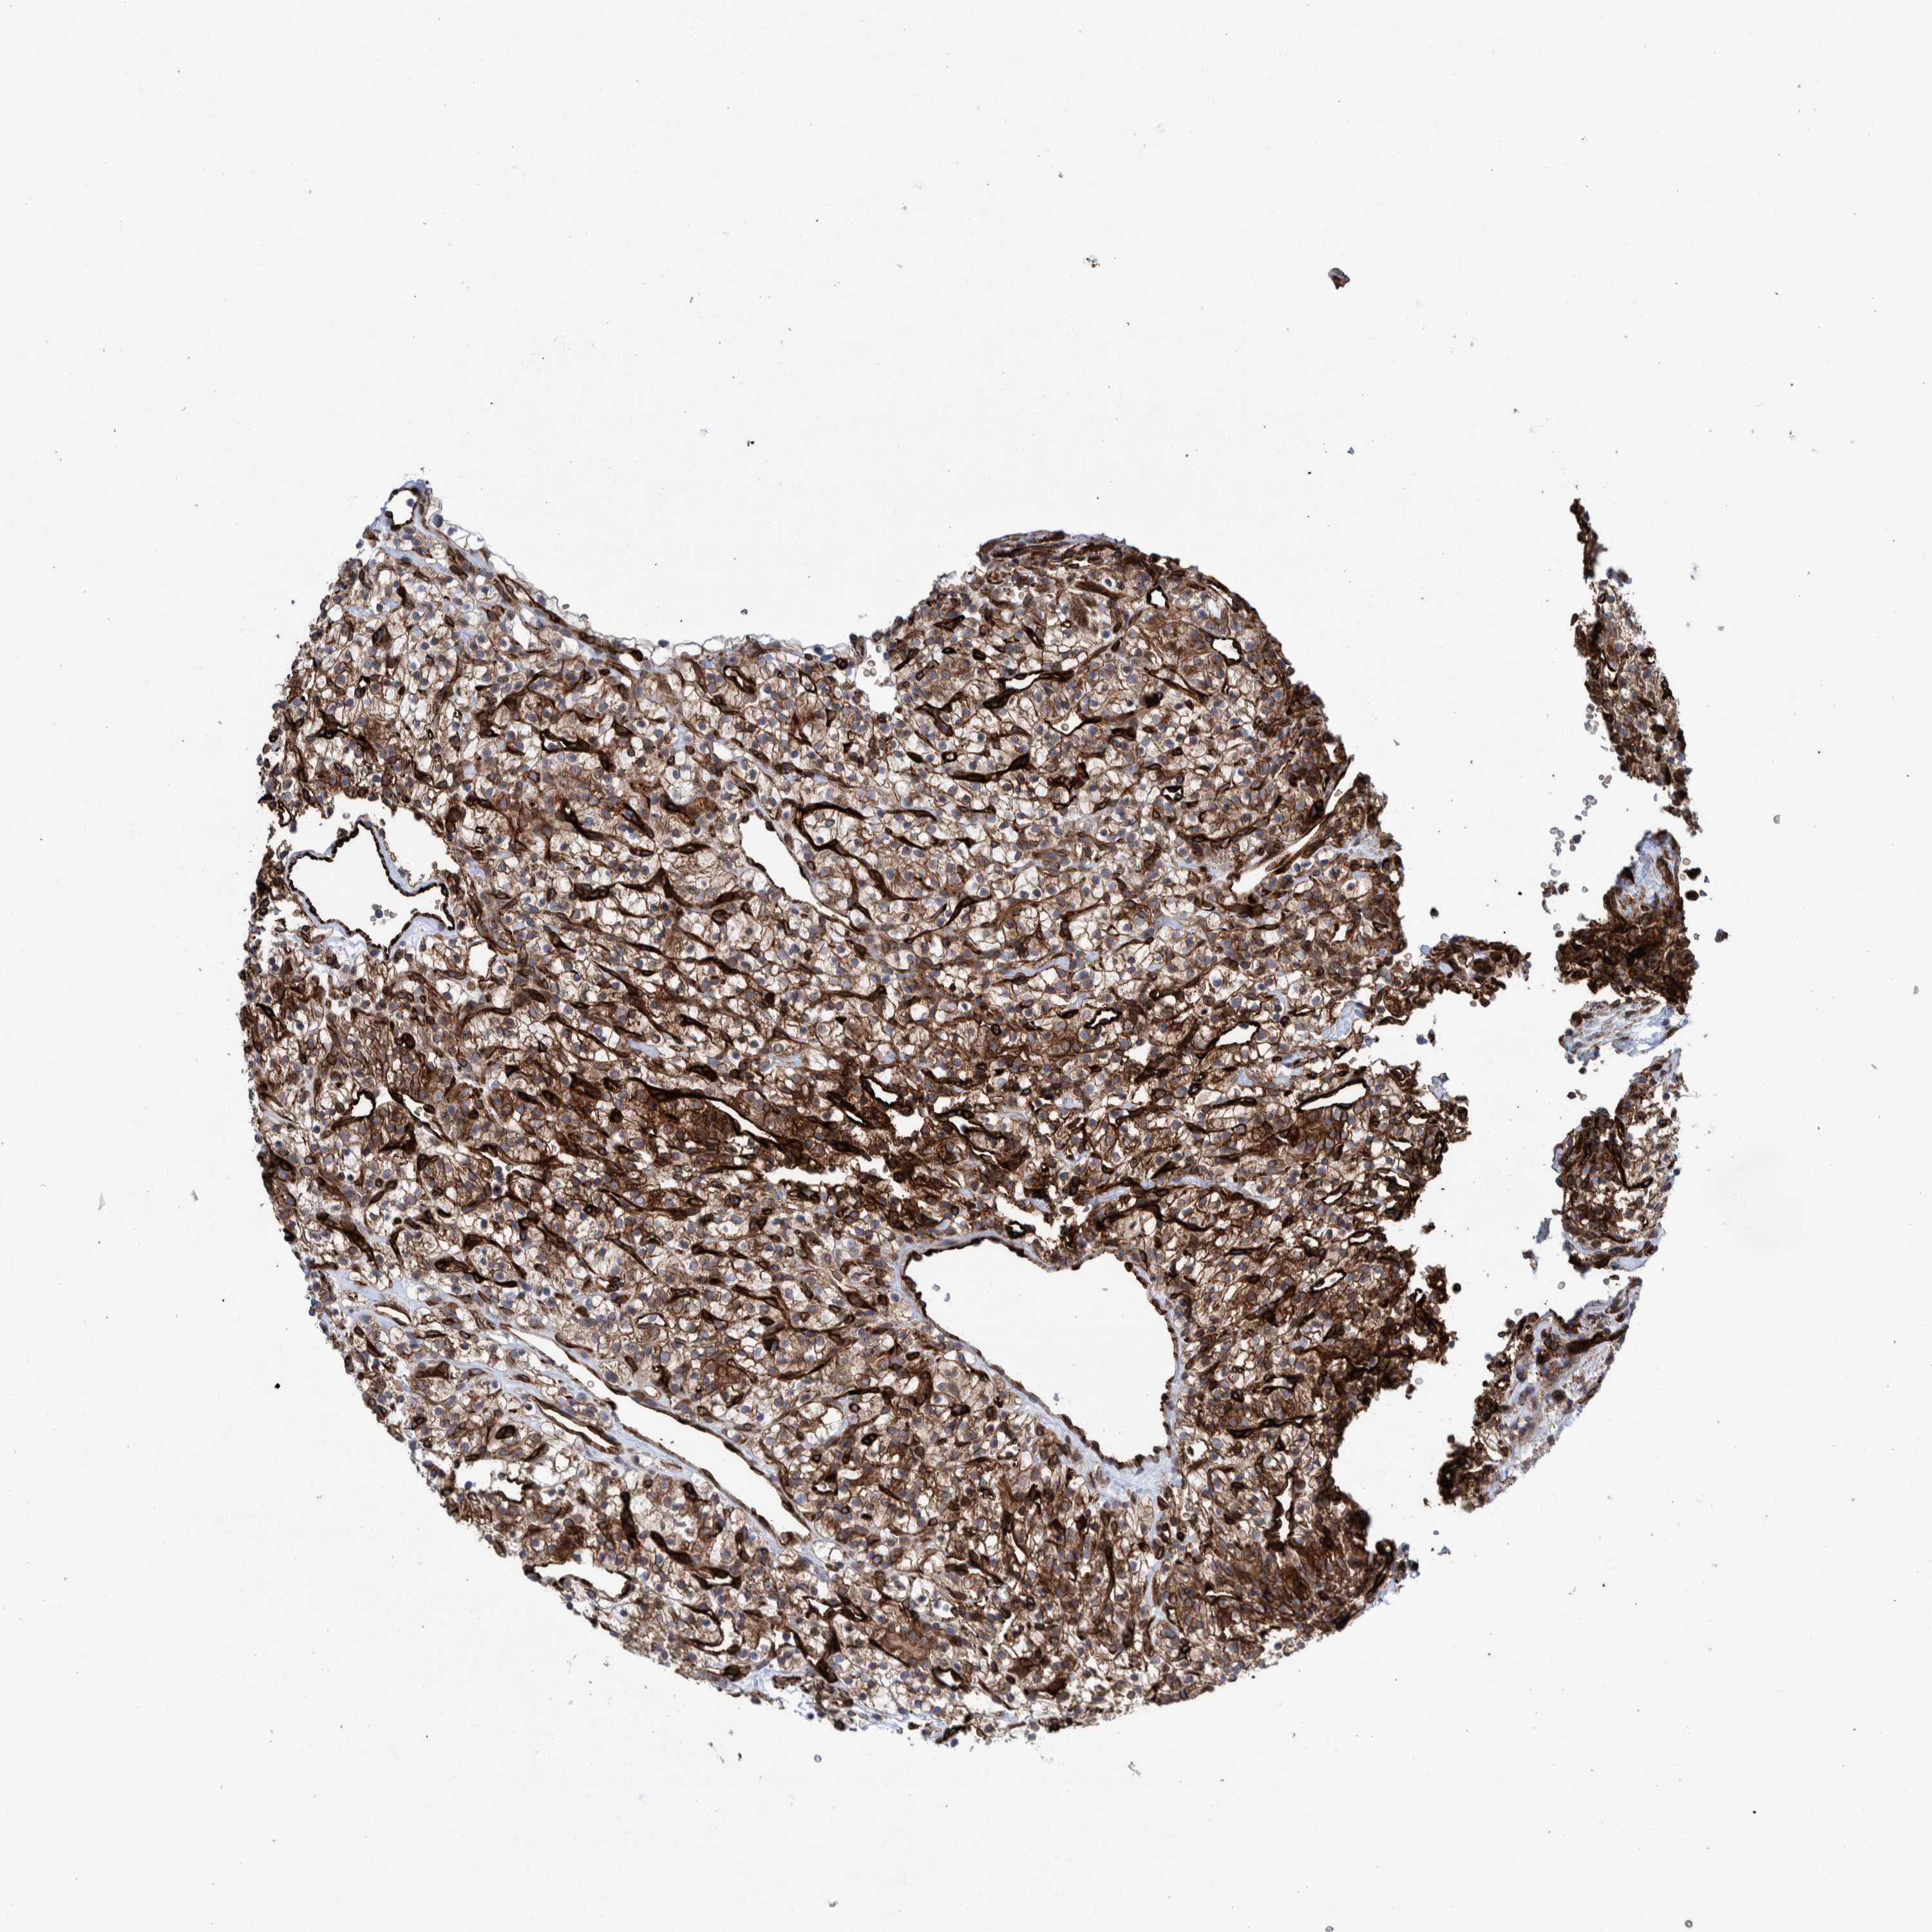

KIDNEY RENAL PAPILLARY CELL CARCINOMA (TCGA) - Interactive survival scatter ploti

The Survival Scatter plot shows the clinical status (i.e. dead or alive) for all individuals in the patient cohort, based on the same data that underlies the corresponding Kaplan-Meier plots. Patients that are alive at last time for follow-up are shown in blue and patients who have died during the study are shown in red.

The x-axis shows the expression levels (FPKM) of the investigated gene in the tumor tissue at the time of diagnosis. The y-axis shows the follow-up time after diagnosis (years). Both axes are complimented with kernel density curves demonstrating the data density over the axes. The top density plot shows the expression levels (FPKM) distribution among dead (red) and alive patients (blue). The right density plot shows the data density of the survived years of dead patients with high and low expression levels respectively, stratified using the cutoff indicated by the vertical dashed line through the Survival Scatter plot. This cutoff is automatically defined based on the FPKM cutoff that minimizes the p-score. The cutoff can be changed by dragging the vertical line or by entering a cutoff value in the square labeled "Current cut-off".

Under the Survival Scatter plot the p-score landscape (black curve; left axis) is shown together with dead median separation (red curve; right axis). Dead median separation is the difference in median mRNA expression between patients who have died with high and low expression, respectively. It is calculated as follows: median FPKM expression of dead patients with high expression - median FPKM expression of dead patients with low expression. This is intended to aid the user in visually exploring custom cutoffs and the associated p-scores and dead median separation.

Individual patient data is displayed and can be filtered by clicking on one or more of the category buttons on the top of the page. Categories describing expression level and patient information include: high, low, alive, dead, female, male and tumor stages. The scale of the x-axis can be toggled between linear and log-scale by clicking on the "x log" button. Mouse-over function shows TCGA ID, patient information and mRNA expression (FPKM) for each patient.

& Survival analysisi

Kaplan-Meier plots summarize results from analysis of correlation between mRNA expression level and patient survival. Patients were divided based on level of expression into one of the two groups "low" (under cut off) or "high" (over cut off). X-axis shows time for survival (years) and y-axis shows the probability of survival, where 1.0 corresponds to 100 percent.

THEM6 is not prognostic in Kidney Renal Papillary Cell Carcinoma (TCGA)

Best expression cut offi

Based on the FPKM value of each gene, patients were classified into two groups and association between prognosis (survival) and gene expression (FPKM) was examined. The best expression cut-off refers the FPKM value that yields maximal difference with regard to survival between the two groups at the lowest log-rank P-value. Best expression cut-off was selected based on survival analysis .

When clicking on this number, the vertical dashed line indicating cut-off, the interactive survival plot, and the Kaplan-Meier curve will be adjusted to show results based on the best expression cut-off.

: 17.44